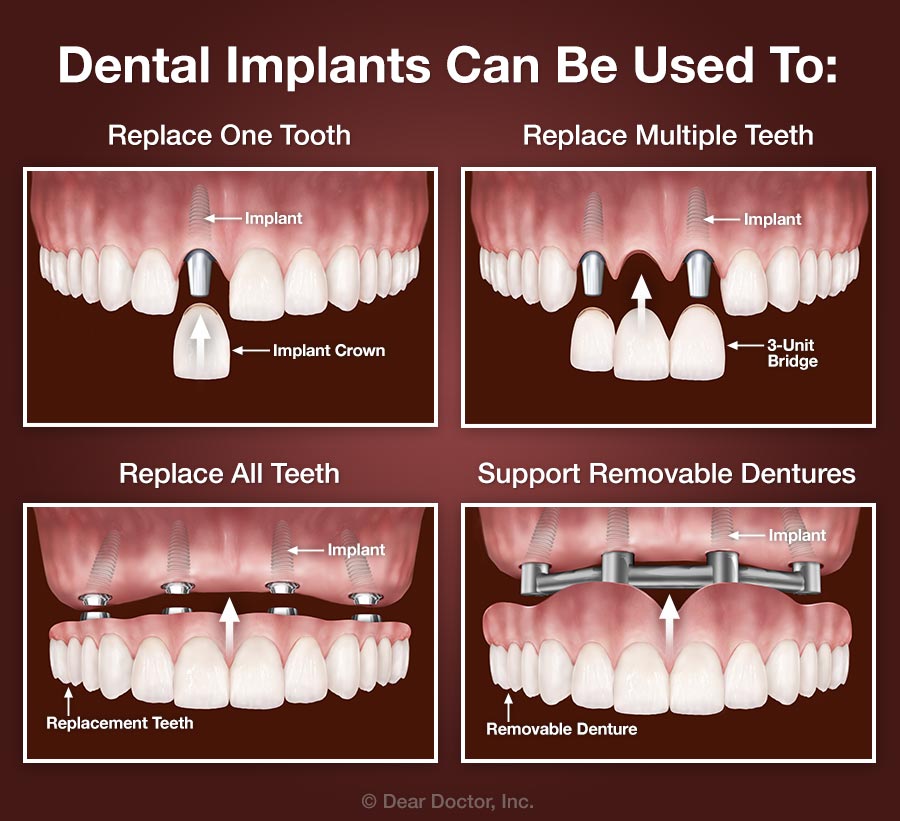

Dental Implants Merrick NY | Replace Missing Teeth | Implant Dentist

Implant Supported Dentures: All you need to know | bellevuerx.com

Discussing: Replacing Missing Teeth With Dental Implants

All Teeth On 4 Dental Implants Sydney | Full Mouth Fixed Dental …

3 on 6 Dental Implants | 70% Less | All-Inclusive Costs

Multiple Dental Implants Claremont CA | Teeth Implants

Dental Implants vs. Dentures – Brooklyn Implant Dentist